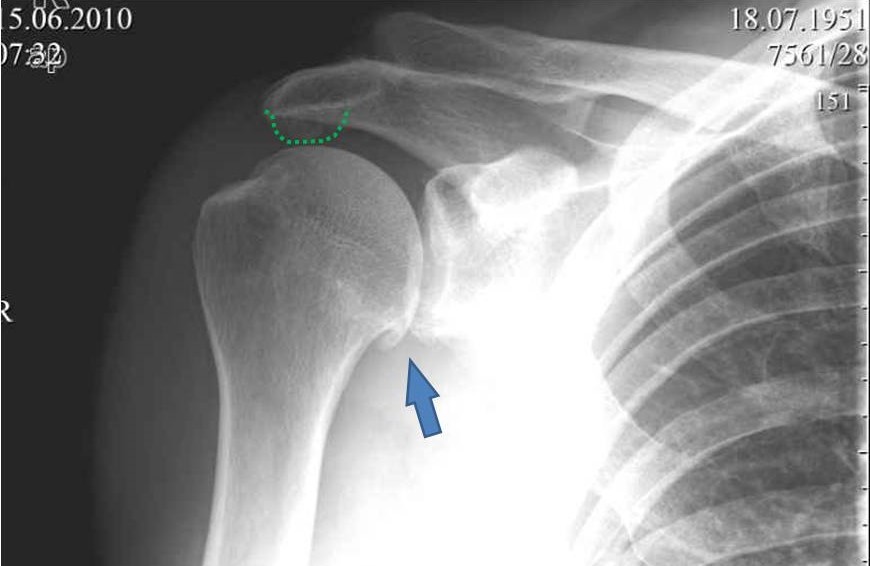

Пациент, мужчина, 59 лет обратился в июне с жалобами на умеренные периодические боли и хруст в области правого плечевого сустава. В анамнезе - 1,5 года назад упал, ударился задней поверхностью локтевого сустава, при отведенной правой руки в плечевом суставе и согнутом в локтевом. Обратился за мед. помощью, по месту жительства, сказали, что ничего страшного, повесили травмированную конечность на косынку.Тогда, в июне 2010года, когда я впервые увидел пациента, он щадил руку, было ограничение объема движений в правом плечевом суставе. Потому я предложил заняться лечебной физкультурой а потом посмотреть достигнутый результат.Сегодня в пациента восстановлен полный объем движений в правом плечевом суставе, боли сохраняются, но не такие выраженные, как раньше.Но при движении правой рукой стоит ТАКОЙ хруст, что слышен на расстоянии. Пальпаторно, при движении правой рукой,ощущается подвижность в акромиально-ключичном сочленении, и боли при отведении в правом плече более 120 градусов.Пациента не устраивает нынешние положение дел с его плечом. Хочет более радикального лечения.Я подумывая об операции, но побаиваюсь за результат. Нужно иссечь рубцы, низвести акромиальный конец ключицы (а она будет "пружинить")и фиксировать крючковидной пластиной к акромиону, не исключается выполнение акромионопластики. Удержит ли пластина и удержатся ли взаимоотношения в акромиально-ключичном сочленении, после удаления пластины?Тут вспомнился разговор с профессором Джолдасом Кулджановым, о необходимости восстановления клювовидно-ключичной связки. Хотелось бы освежить этот разговор в своей памяти и попросить профессора найти время и рассказать еще раз о целесообразности и технике восстановления клювовидно-ключичной связки, ну выслушать мнение коллег по Ортофоруму.С уважением Шушания Батал.

На представленном снимке нет данных за повреждение акромиально-ключичного сустава.

Возможно у вашего пациента было какое-то повреждение АКС. Об этом говорит

состояние небольшого подвывиха, вторая степень - суставные поверхности

находятся друг против друга с небольшим смещением ключицы. Смещение

оценивается по нижней поверхности АКС. Но на рентгеновском снимке бросается

в глаза дегенеративные изменения. Первый из них это остеофит в нижней части

головки плеча (французская бородка) помечен стрелкой. Эта находка говорит о

артрозе плечелопаточного сустава. Вторая находка большой остеофит

акромиального отростка - помечен пунктирной линией. Данная находка говорит о

существующем давлении на сухожилия манжетки вращателей и вероятно разрыв

сухожилий. Rotator cuff syndrome Rotator cuff tear. Полный разрыв сухожилий

может объяснить хруст при движении в плечевом состоянии.